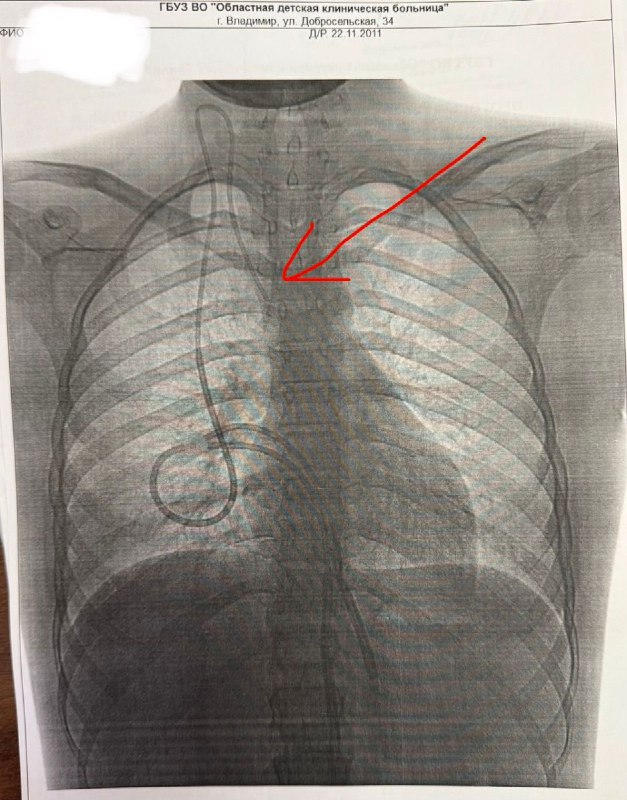

Во Владимире детям с онкологией установили долгосрочные катетеры для химиотерапии https://newsvladimir.

Фото - @newsvladimirru